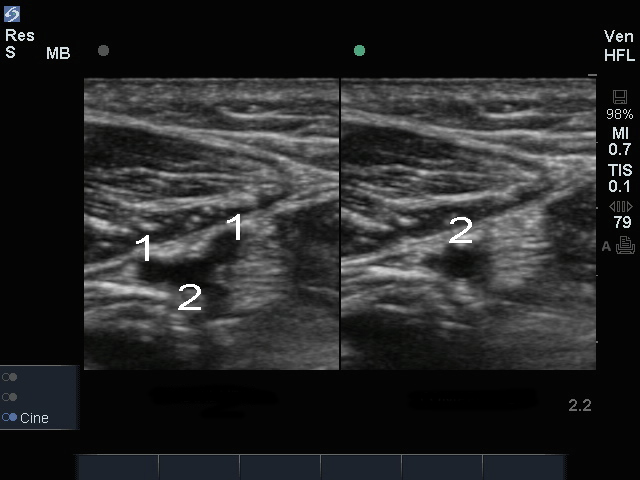

受压迫的桡静脉图像

左侧:桡静脉

右侧:受压迫的桡静脉

静脉

动脉